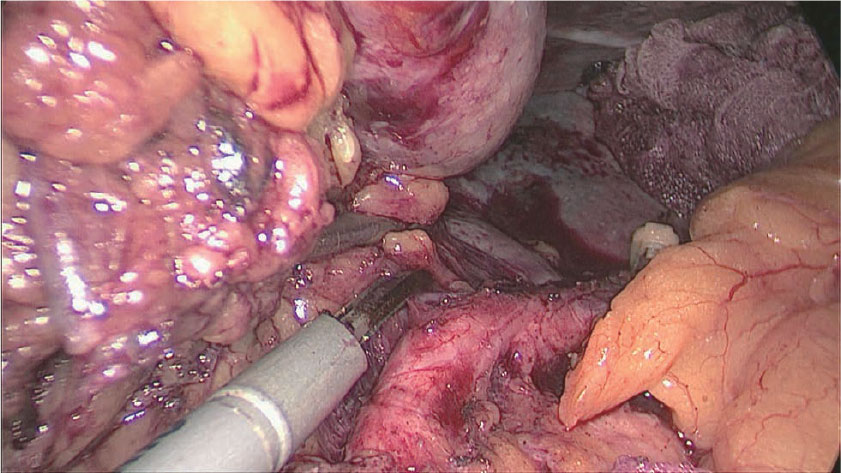

5)No.10,11dリンパ節郭清

ここから膵後筋膜を広く観察することができ、この正確な剥離によって背側胃間膜を間膜化でき、この中から脾動脈神経叢を温存する層で腹側と背側の両方からNo.11pd,10リンパ節を郭清する。

次に脾門部の郭清に移るが、まず脾下終末枝より動脈走行の確認を行う。膵尾動脈は通常約3/4程度確認でき、先の下終末枝や左胃大網動脈(LGEA)から分枝する。この下終末枝からの分枝の場合、膵上縁から丁寧に同動脈周囲の脂肪組織を切離していくと同定しやすい。脾下終末枝周囲の郭清をやや中枢に戻り、LGEAの根部の同定を行う。LGEAは脾動脈の分枝の中でも最も変異性が強くその根部は脾動脈、分岐部、下終末動脈に及ぶため、この切離はその周囲の血管走行が十分把握できてから行う。

下終末枝から脾動脈本幹周囲へと郭清を進めると上終末枝の同定ができ、この動脈沿いに脾門の上方へと切離を進め短胃動静脈を確認し根部で切離する。またNo.10の郭清では、脾動脈周囲の神経叢や神経束を温存し、これを把持牽引することで視野展開に利用している。

脾動脈分岐部より中枢に郭清を進めると脾動脈が上方へ緩やかに湾曲する部分があり同部位のやや遠位で大膵動脈を確認できる場合が多い。この部位では脾動静脈間が離れその間にリンパ節(No.11d)が存在することが多く、同部の郭清は腹側と背側の両方から行っている。このやや近位で後胃動静脈が分枝することが多く、中枢からと抹消からの郭清を完結させる。